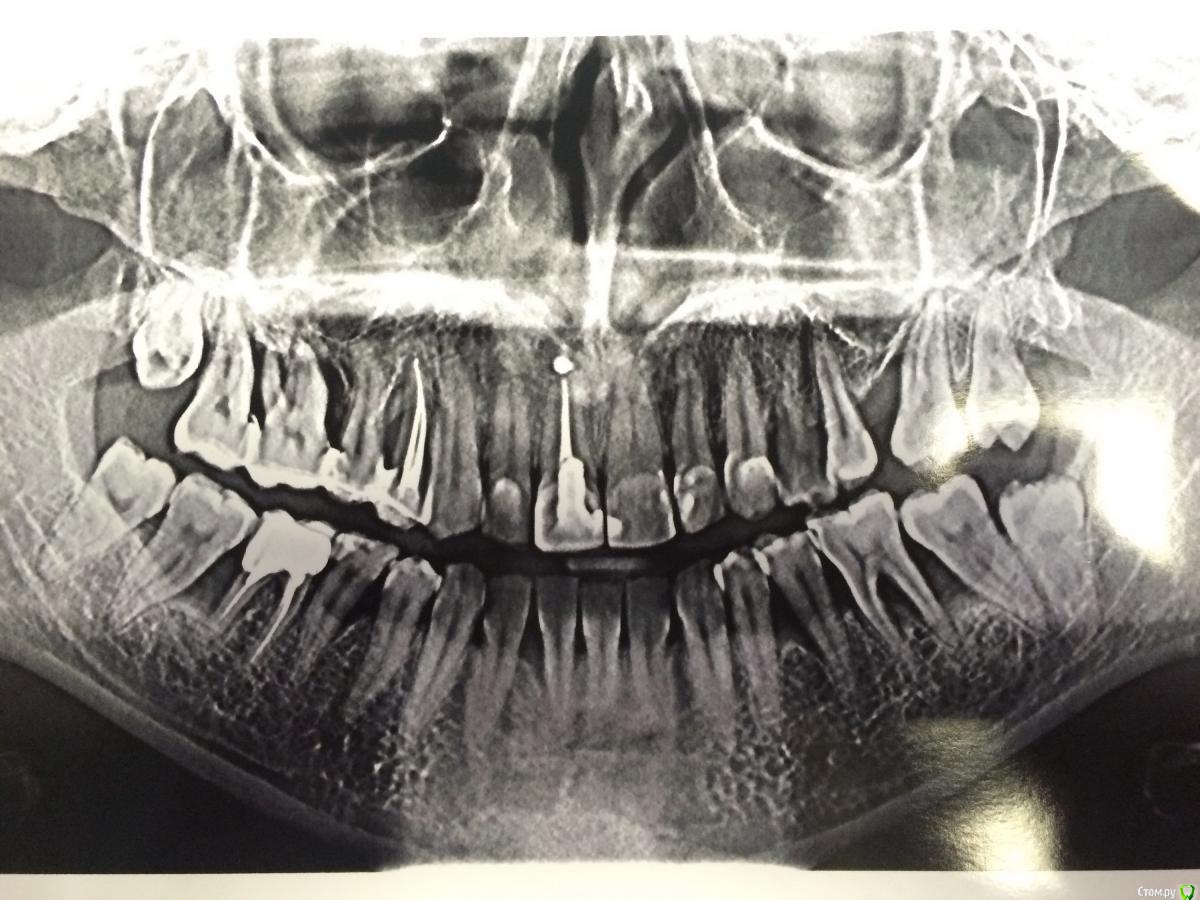

faity Опубликовано 22 октября, 2015 Поделиться Опубликовано 22 октября, 2015 судя по этому снимку удалять 1.8,1.7,1.6, 2.6, 2.7, 2.8, 3.8, 3.7, 3.6, 3.5, 4.5, 4.6, 4.7, 4.8сделайте КТ 1 Ссылка на комментарий

Jurai Опубликовано 22 октября, 2015 Поделиться Опубликовано 22 октября, 2015 Восьмерки здесь не виноваты, и на их сохранение для того, чтобы они "заняли место" рассчитывать не надо, не займут. Лоскутные операции в боковых отделах не особенно эффективны будут, учитывая общее состояние тканей. Безжалостно удаляйте безнадежные зубы, пока хоть немного кости осталось - для дальнейшего протезирования, вверху справа уже изрядно непростая ситуация. Под удаление 18, 17, 16, 15, 14, 27,28, 38,37, 36, 35, 45, 46, 47, 48. Начните обследование с эндокринолога и гастроэнтеролога. 1 Ссылка на комментарий

Bier Опубликовано 24 октября, 2015 Поделиться Опубликовано 24 октября, 2015 судя по этому снимку удалять 1.8,1.7,1.6, 2.6, 2.7, 2.8, 3.8, 3.7, 3.6, 3.5, 4.5, 4.6, 4.7, 4.8сделайте КТя бы побольше зубов сохранил.Согласен по 18,17,17, 14(26 зуба нет) 27,28 . 38,36,46, ну и 48 за ненадобностью.Остальные нужно сохранять. Вы уж слишком агрессивно замахнулись. Ссылка на комментарий

faity Опубликовано 26 октября, 2015 Поделиться Опубликовано 26 октября, 2015 я бы побольше зубов сохранил.Согласен по 18,17,17, 14(26 зуба нет) 27,28 . 38,36,46, ну и 48 за ненадобностью.Остальные нужно сохранять. Вы уж слишком агрессивно замахнулись.Олег, так я же написал: "по этому снимку" там пародонтальные карманы на 1/2- 2/3 длины корня.поэтому я за КТ в первую очередь Ссылка на комментарий